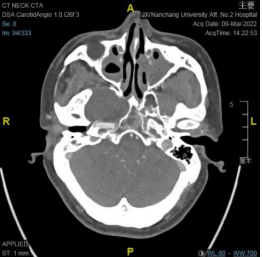

右侧鞍旁见类圆形占位,中央稍低密度,周围环形稍高密度,可见残留骨质密度影,大小约 32☓46 mm,邻近骨质吸收变薄,建议 MRI 平扫+增强扫描。

中颅窝右侧鞍旁可见无强化稍低密度影,边缘可见少许钙化影,边界清晰,邻近骨质受压变薄,邻近颈内动脉受压内移。

从 MRI 增强扫描上肿块无强化,可与神经鞘膜瘤相鉴别;CTA 成像无强化环及强化结节表现,肿块将颈内动脉向后推挤,MRI 增强也无病变周边高信号环及典型的动脉搏动伪影表现,这些影像学表现上可与动脉瘤相鉴别。